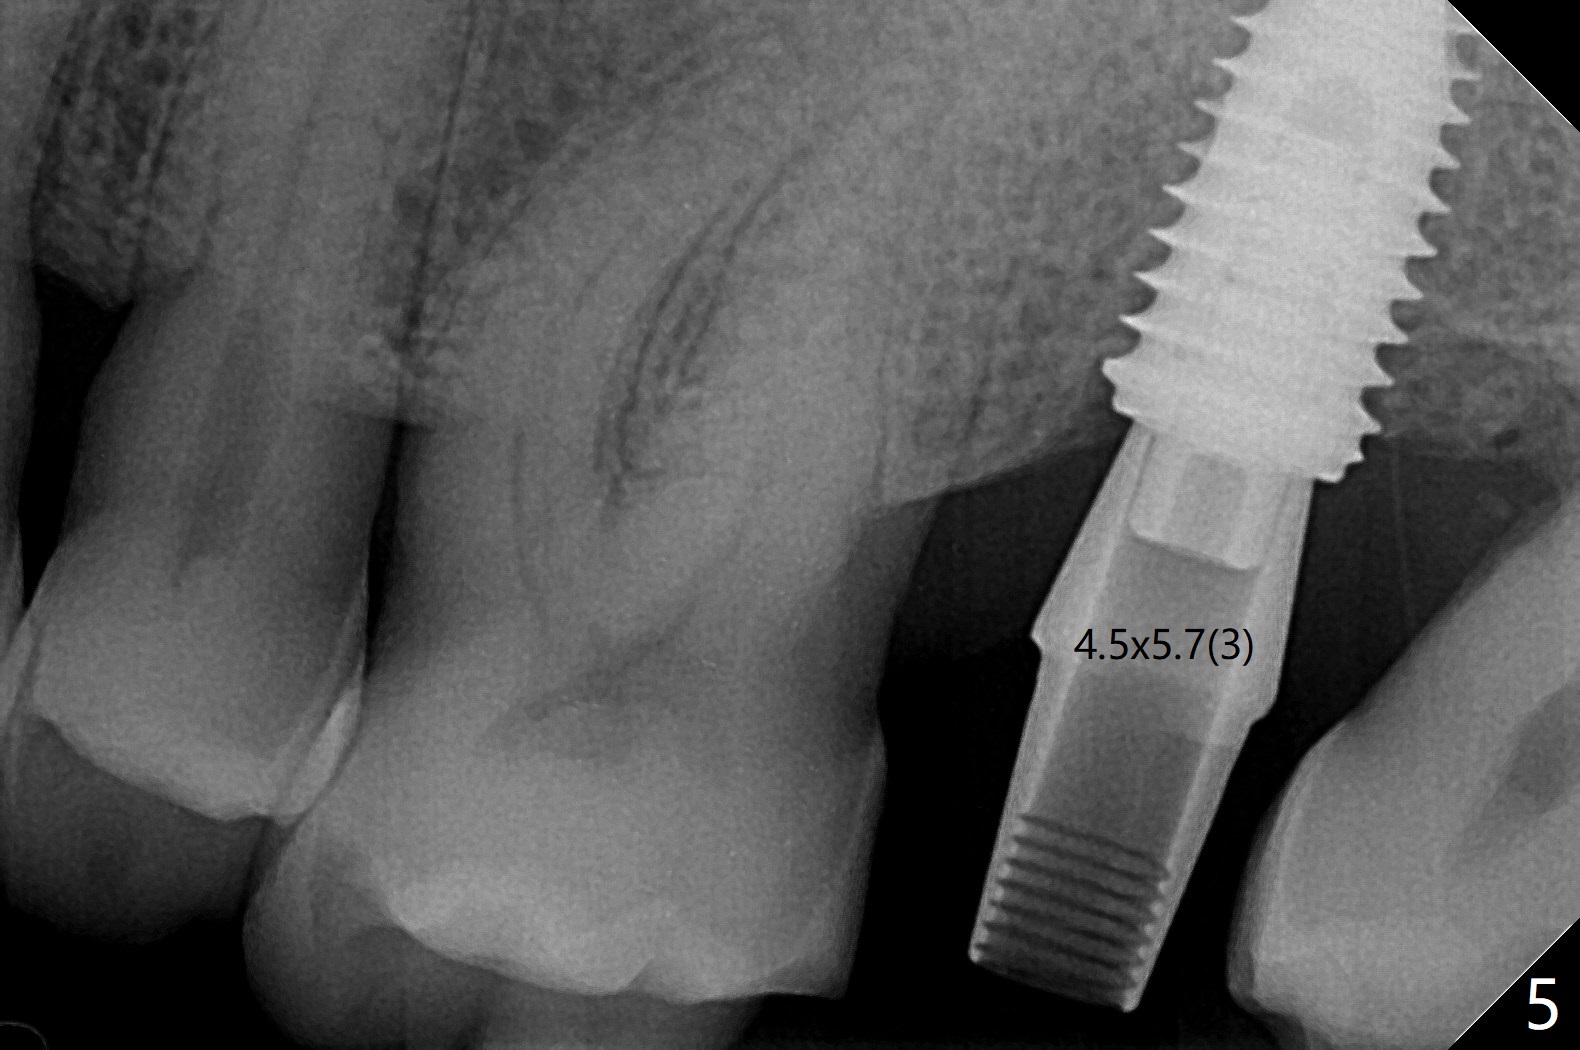

For the narrow mesiodistal space (Fig.3), a 4.5x4.5(3) mm cementation abutment is placed for final restoration. He expresses interest in implants at #29 and 30 or #19. The screw is loose 2 years 5 months post cementation; the crown/abutment is incompletely seated after proximal reduction of the crown (Fig.4). Due to the narrow space, a new abutment appears to be easier to be seated (Fig.5). When the permanent crown is delivered, the distal contact is loose, probably related to ill-fitting temp. The permanent crown is cemented with temp bond. Return to Upper Molar Immediate Implant, Armaments, Guide for 29/30 Torque Xin Wei, DDS, PhD, MS 1st edition 05/11/2018, last revision 04/19/2021